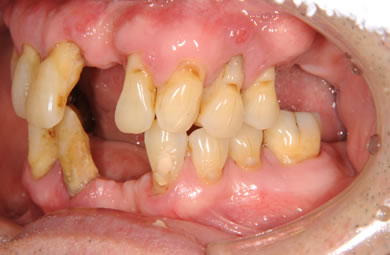

インプラントの症例写真 IMPLANT

骨再生スピードインプラント治療+AGC連結セラミック治療+セラミック治療

| 性別/年齢 | 男性 / 61歳 | ||||||||||||||||||||||||||||||||

| 主訴 | 歯周病の治療およびインプラント治療や義歯治療について相談したい。 | ||||||||||||||||||||||||||||||||

| 治療方針 | ソケットリフト法により上顎洞底部を拳上することにより、骨の無い部分に骨をつくってあげ、インプラント治療を可能にする。さらに歯周病により組織の破壊が著しいので、AGC連結セラミック治療により上顎の審美的回復を行う。 | ||||||||||||||||||||||||||||||||

| 治療内容 | インプラント7本(抜歯AGC即日スピードインプラント+ソケットリフト)、AGCハイブリッドセラミック連結ブリッジ1装置(上顎)ハイブリッドセラミック8本 | ||||||||||||||||||||||||||||||||